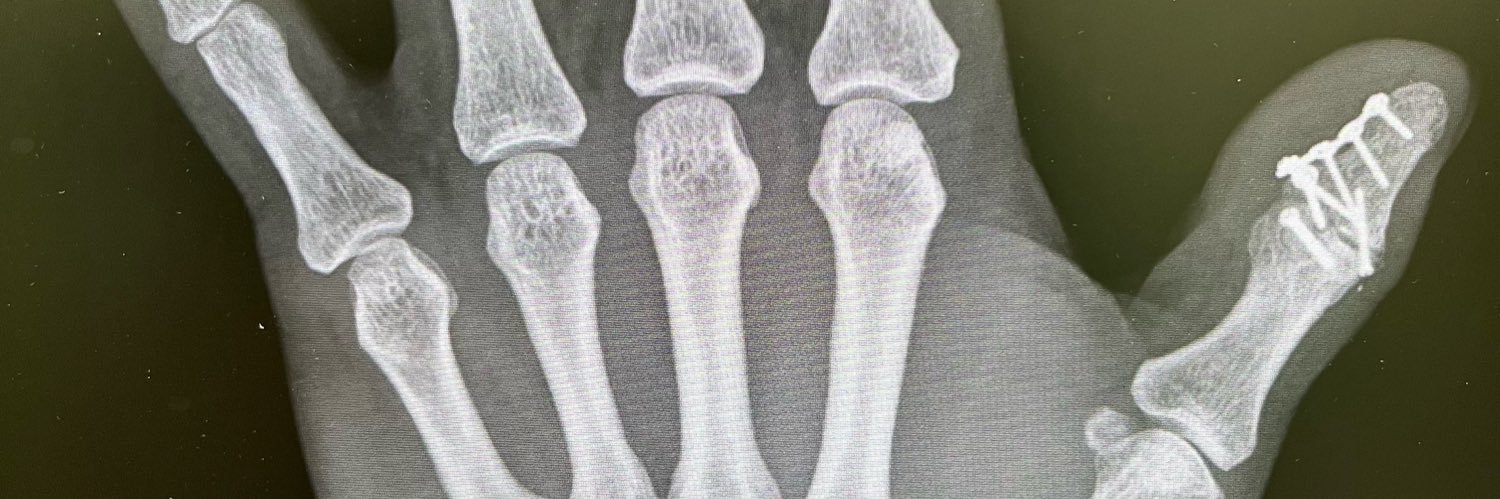

今年60歳還暦…車騎星3つ持ちのB型 髙橋幸宏さんの影響を受けドラムを初めるが手のケガで叩けなくなる… 30年振りに同級生とバンドを組みドラムを叩くの再開。仕事で酷使した手の親指の粉砕骨折、腱鞘炎、バネ指、母指CM関節症を持ちながら奮闘中🥁 古神道に興味があり、山蔭神道のお作法を学んだ。